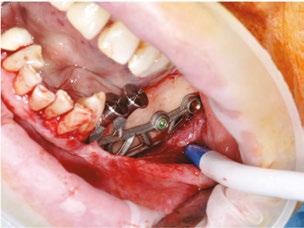

The procedure begins with local anesthesia at multiple points, vestibular and lingual, from the symphyseal region to the ascending ramus. However, an infiltration in the lingula of the mandible is not necessary. The incision is performed using the technique described above (Figures 5A and 5B).

It is imperative to carefully reflect a full-thickness flap following the periosteum. After reflection, an atraumatic periosteal expansion using a soft brush (Figure 6) will allow for the flaps to be repositioned without tension over the implant and bony surfaces at the end of the procedure.

Figures 8A-8D: Placing the subperiosteal implant and monitoring its adaptation Figures 5A and 5B: 5A. Initial clinical view. 5B. Access flap Figure 6: Periosteal expansion using a soft brush Figure 7: Prehension of the subperiosteal implant

After the soft tissue is prepared, the bony surface is carefully cleaned. For easy insertion, the healing abutments are left in place, and the implant is held firmly with hemostatic forceps (Figure 7). The implant is inserted via distal translation in the direction of the angle of the mandible, then a mesio-anterior rotation. The surgeon must control the lack of mobility and the adaptation of the implant to the bony surface at all points (Figures 8A, 8B, 8C, and 8D).